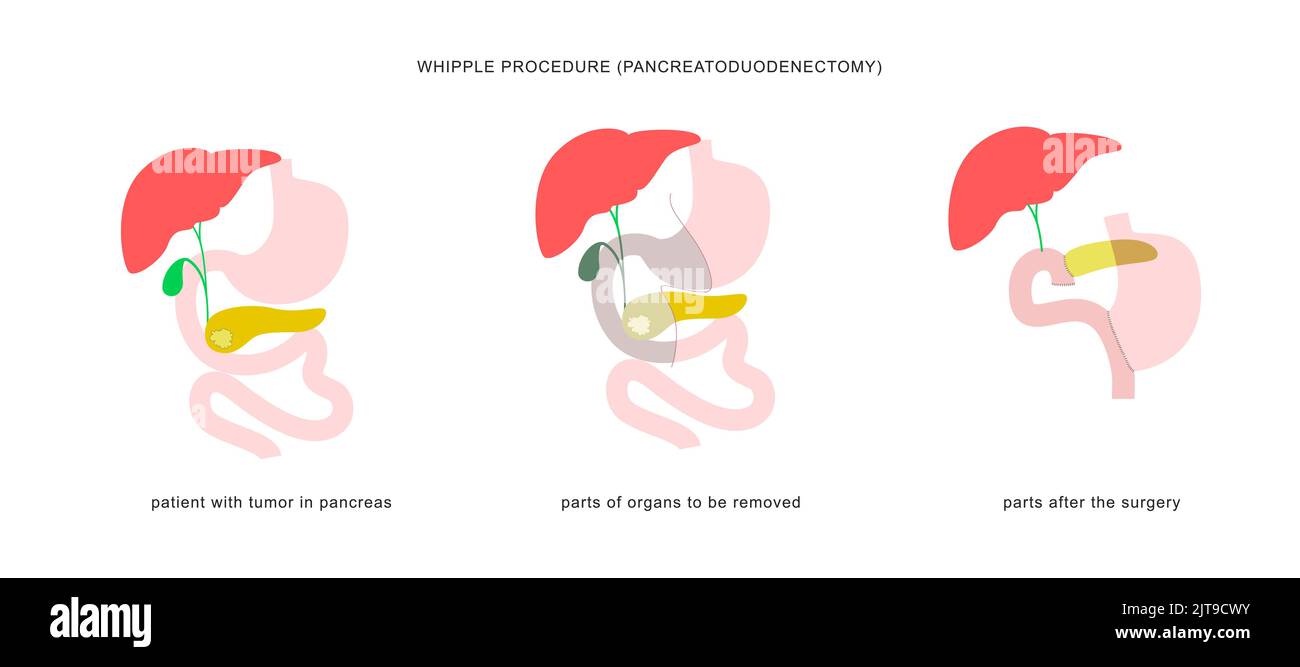

Whipple Procedure Diagram

Whipple Procedure Steps

Whipple Procedure Diagram